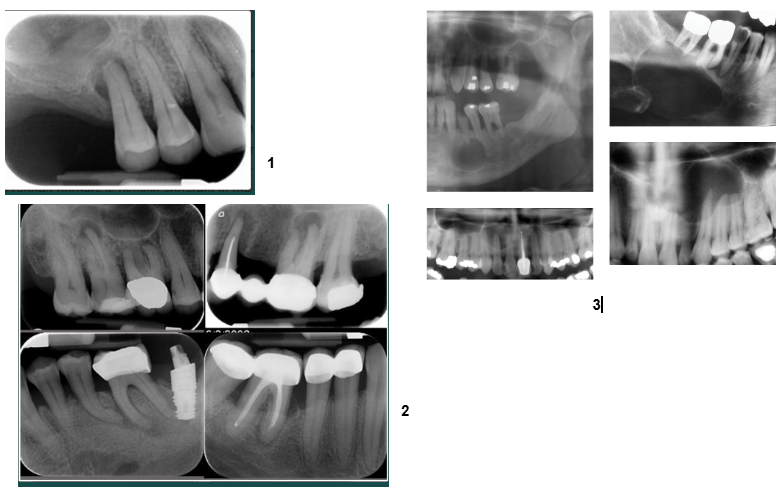

all periapical RL linked with non vital teeth=necrosis

can’t definitively differentiate radiographically

radiographic tendencies (not diagnostic)

abscess-PDL widening, diffuse borders

granuloma-small, well defined RL

cyst-larger, may show corticated border

diagnosis requires clinical tests (vitality testing) and/or biopsy